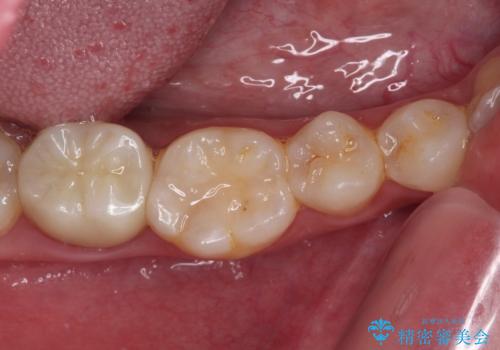

根管治療や歯周外科処置後にフルジルコニアクラウンにて補綴治療することとしました。

再発や他の歯がむし歯となるリスクを低減させるため、日頃からのプラークコントロールと定期的なクリーニングが重要となります。